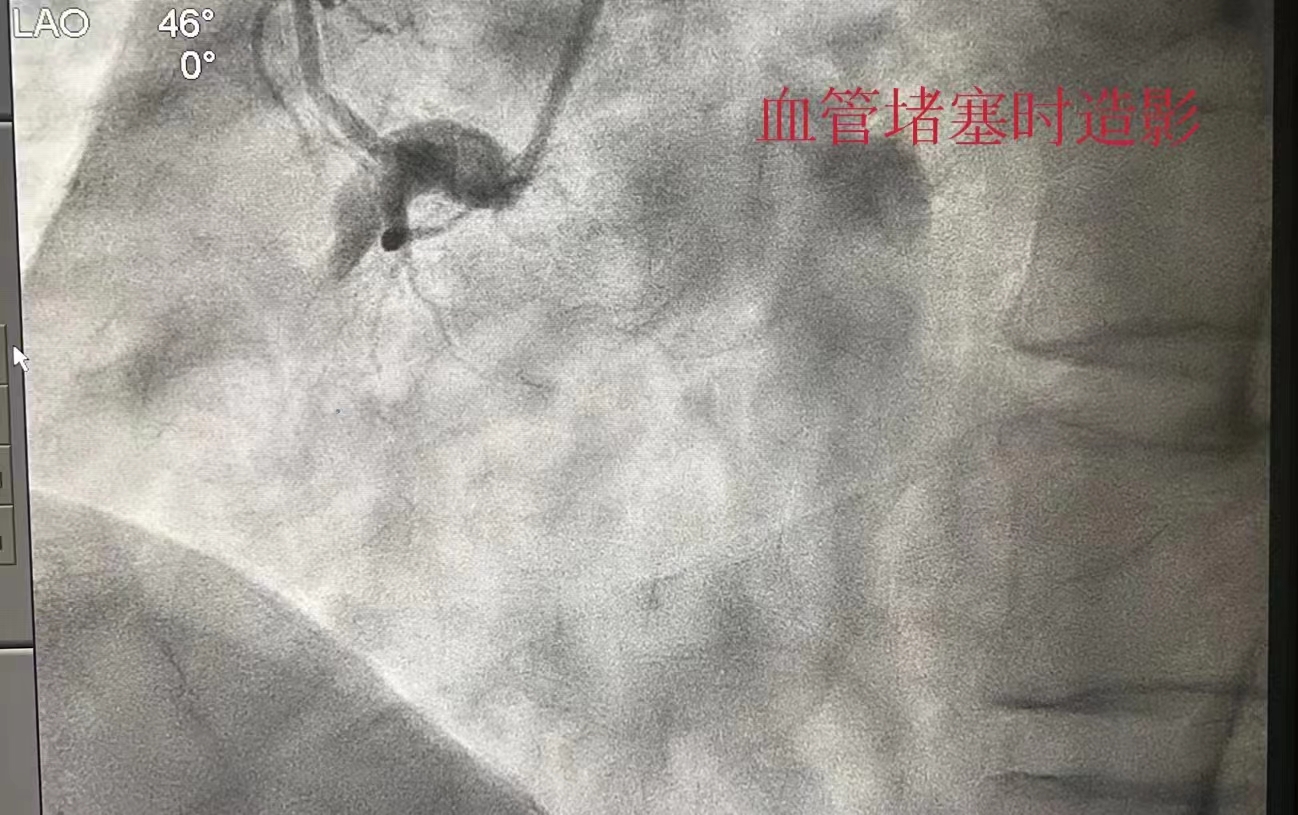

半个月前的一个傍晚,宋先生在工作中突感胸闷、喘不上气,逐渐出现胸口痛、出汗的情况,同事立即将他送至附近医院就诊,心电图检查考虑急性下壁心肌梗死,通过绿色通道转往捷克论坛 ,以最快的时间完成急诊造影,造影显示右冠状动脉堵塞,立即手术开通血管,宋先生转危为安。